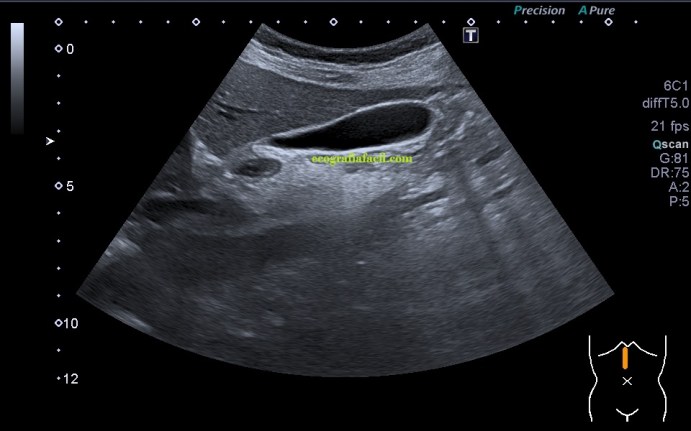

La paciente presentaba una vesícula muy normal, pero escondía tesoros, dos concretamente. Tras un aspecto sacular y anecoico, con una transmisión de sonido muy bonita, se presentaban dos aspectos ecográficos, primero te enseño las imágenes y luego te explico, ¿quieres?…

En la imagen 1 la ecoestructura era absolutamente normal, sacular, alargada y anecoica en longitudinal, pero en la imagen 2 se presenta una estructura en una forma anómala, variante de la normalidad, que en ecografía se denomina «vesícula en gorro frigio», su aspecto recuerda a este tipo de gorros de forma cónica con punta curvada que históricamente han acompañado a la humanidad en multitud de situaciones, te dejo el enlace (cultura general) por si te apetece leer un poco…es curioso.